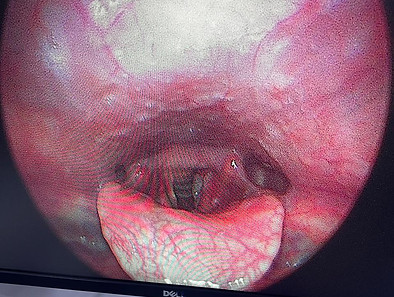

1 - Pathologie de l'oreille et surdité

Au cabinet ORL du Dr Lahssen ELJahd à Inezgane, nous prenons en charge une large gamme de pathologies de l’oreille, allant des infections chroniques aux troubles de l’audition. Grâce à des équipements de pointe et une expertise confirmée, nous assurons un diagnostic précis et un suivi personnalisé.

Que vous souffriez de douleurs auriculaires, d’acouphènes, de vertiges ou d’une perte auditive progressive, le Dr ELJahd vous accompagne dans un parcours de soins adapté à votre situation. Des examens spécialisés (microscopie, audiométrie, etc.) permettent d’identifier la cause exacte et de proposer le traitement le plus efficace, médical ou chirurgical.